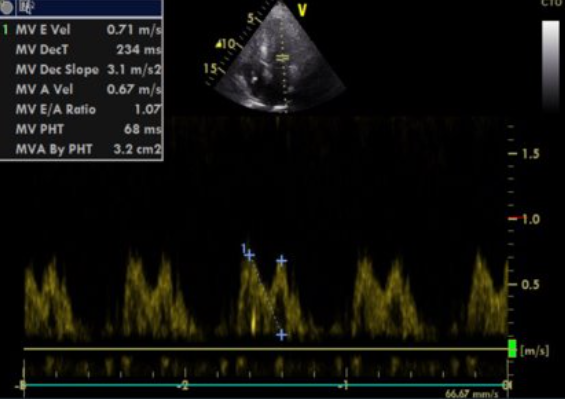

Echokardiogramm:

• TTE: konzentrische und symmetrische Hypertrophie mit „körnig funkelndem“ Erscheinungsbild mit diastolischer Dysfunktion und Klappenverdickung in Verbindung mit Vorhofdilatation und Verdickung des interatrialen Septums.